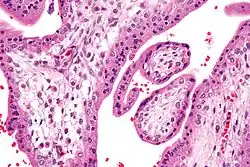

Micrograph of chorionic villi with Hofbauer cells. H&E stain.

Under histology sections, Hofbauer cells have appeared with discernible amount of cytoplasm.